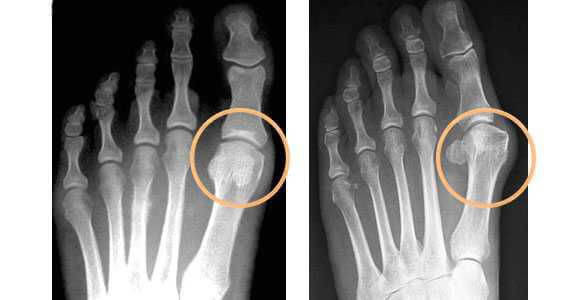

«Hallux abducto valgus» или «Вальгусная деформация первого пальца стопы» - медицинский термин, означающий искривление и отклонение плюснефалангового сустава большого пальца кнаружи.

При этом первая фаланга большого пальца может смещаться над- или под второй палец, а плюснефаланговый сустав выпирает и образует вальгусную «шишку».

- рентгенография стоп в 3-х проекциях - в целях определения стадии заболевания, а также выявления сопутствующих патологий, к которым относятся артроз, подвывих и вывих суставов. Исследование проводится под нагрузкой, так как результат искривления углов может отличаться на 20%. По рентгеновскому снимку проводят все расчеты, необходимые для определения тактики лечения.

Стадии деформации, когда необходим MagnetFox

- Нормальная

стопа

- Начальная стадия

деформации

- Выраженная

деформация

Клинические исследования показали, что новый MagnetFix эффективен как при начальной, так и при выраженной стадии деформации сустава.MagnetFix максимально прост и удобен в использовании